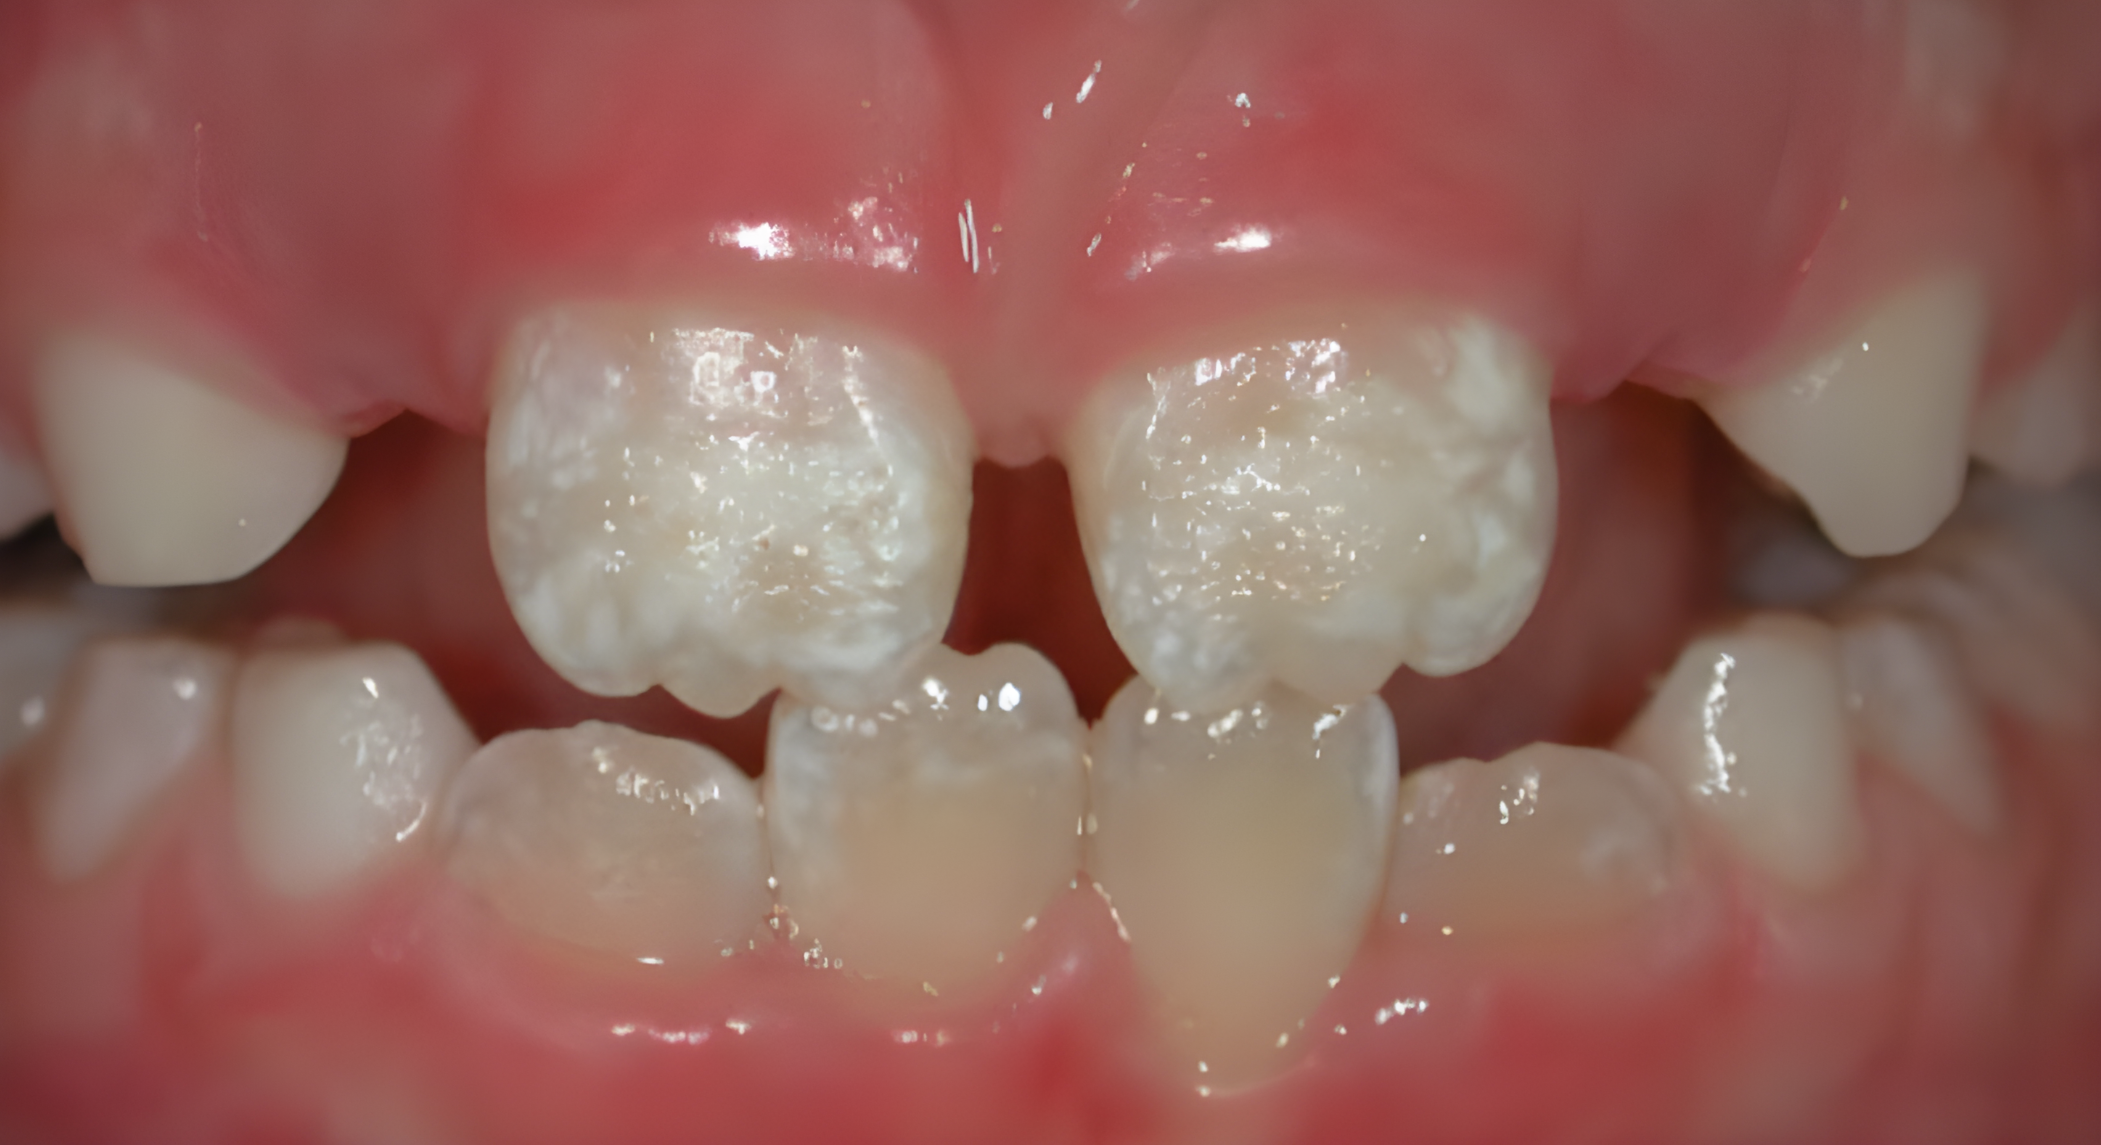

Hypoplastic enamel of the front teeth

Oral symptoms commonly associated with coeliac disease include dental enamel defects, atrophic glossitis, recurrent mouth ulcers and delayed tooth eruption in children.

 Dental enamel defects (or dental hypoplasia) is enamel that’s thinner, pitted or discoloured.